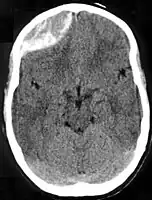

Nontraumatic epidural hematoma in a young woman. The grey area in the top right is organizing hematoma, causing midline shift and compression of the ventricle. Non-contrast CT scan of a traumatic acute hematoma in the right fronto-temporal area.

Non-contrast CT scan of a traumatic acute hematoma in the right fronto-temporal area. A diagram showing an epidural hematoma.